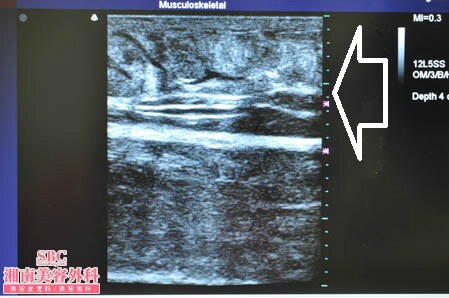

No.177936【脂肪吸引】圧倒的吸引量で圧倒的満足度!あの有名な根こそぎ竹田先生の劇的ビフォーアフター!〜他院の再手術!左太もも3Dタッチビュー〜

施術後術直後

左太もも3Dタッチビュー

まずは3Dタッチビュー(超音波)の出番ですね。

患者様にはこの画像を手術終了後に

見ていただきました。

そしてもちろんご納得いただきました。

皮下脂肪の取り残しがないことが

患者様に画像で見ていただける3Dタッチビュー。

大人気です!!